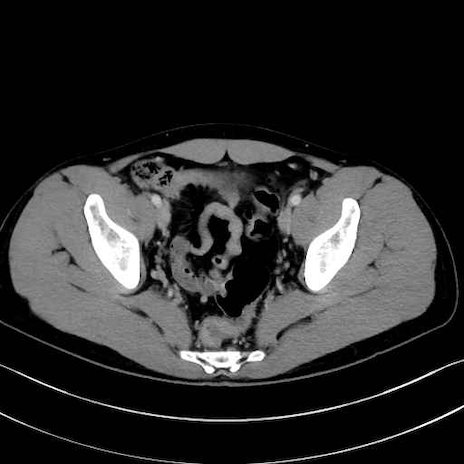

4. 深層外旋六筋(股関節の深部)

梨状筋 (Piriformis)

内閉鎖筋 (Obturator internus)

外閉鎖筋 (Obturator externus)

大腿方形筋 (Quadratus femoris)